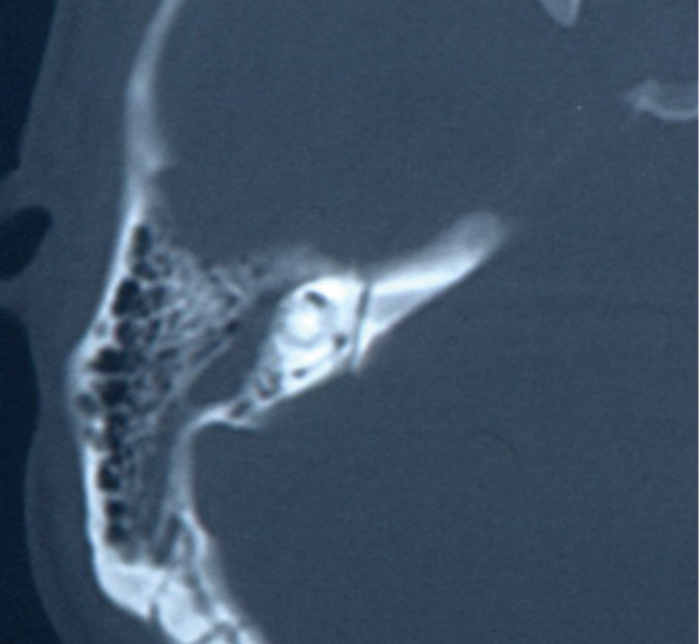

Figure 2: Axial CT scan showing a transverse fracture line running from the posterior

petrous bone across the internal auditory canal (IAC) and medial to the inner ear structures.

Traditionally, fractures have been divided into transverse or longitudinal (Figures 1 and 2). Longitudinal fractures usually arise from lateral blows to the head, with the fracture line following the path of least resistance. Transverse fractures arise from blows to the occipital region. However, numerous studies demonstrated no prognostic value in this classification, with the incidence of true longitudinal fractures rarely occurring, rather an oblique fracture with features of both. More recently, the involvement of the otic capsule (more common in transverse fractures) has been used as a more relevant clinical descriptor, as this allows for the more accurate prediction of associated complications [3, 4].